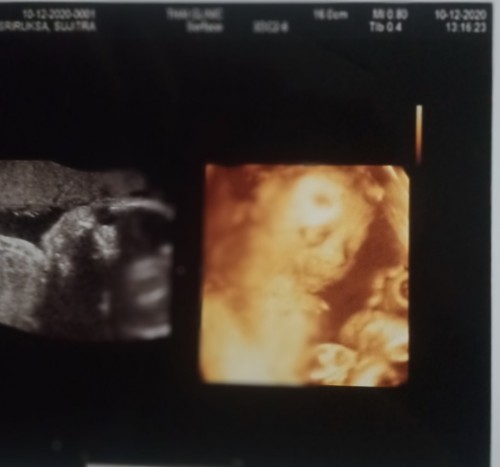

หมอว่าหญิง กำหนดคลอดกุมภาค่ะ

ผู้หญิงคะ คลอดธันวาจ้า❤😍